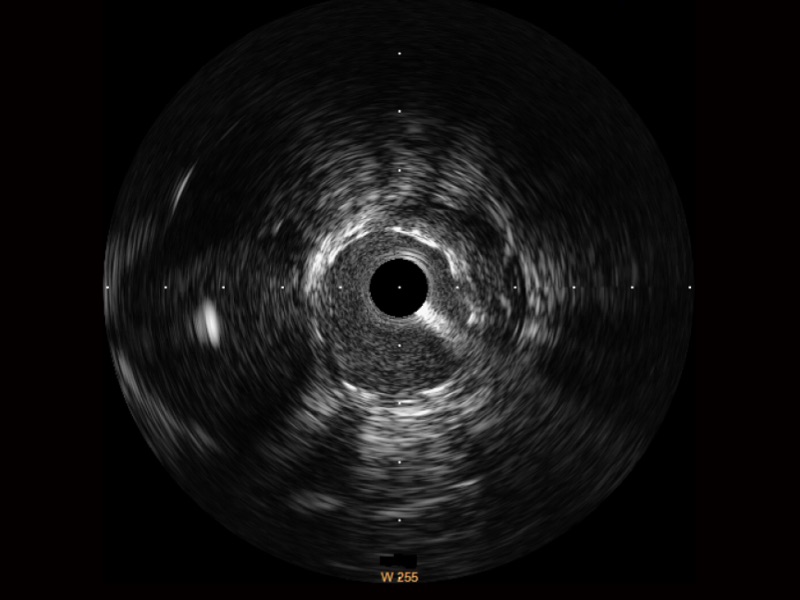

传统IVUS图像

对比传统IVUS导管成像,环球UG官网宽频IVUS图像的近场支架梁显影更细腻,远场中膜外血管仍清晰可辨,兼顾远中近,兼顾分辨力与穿透深度